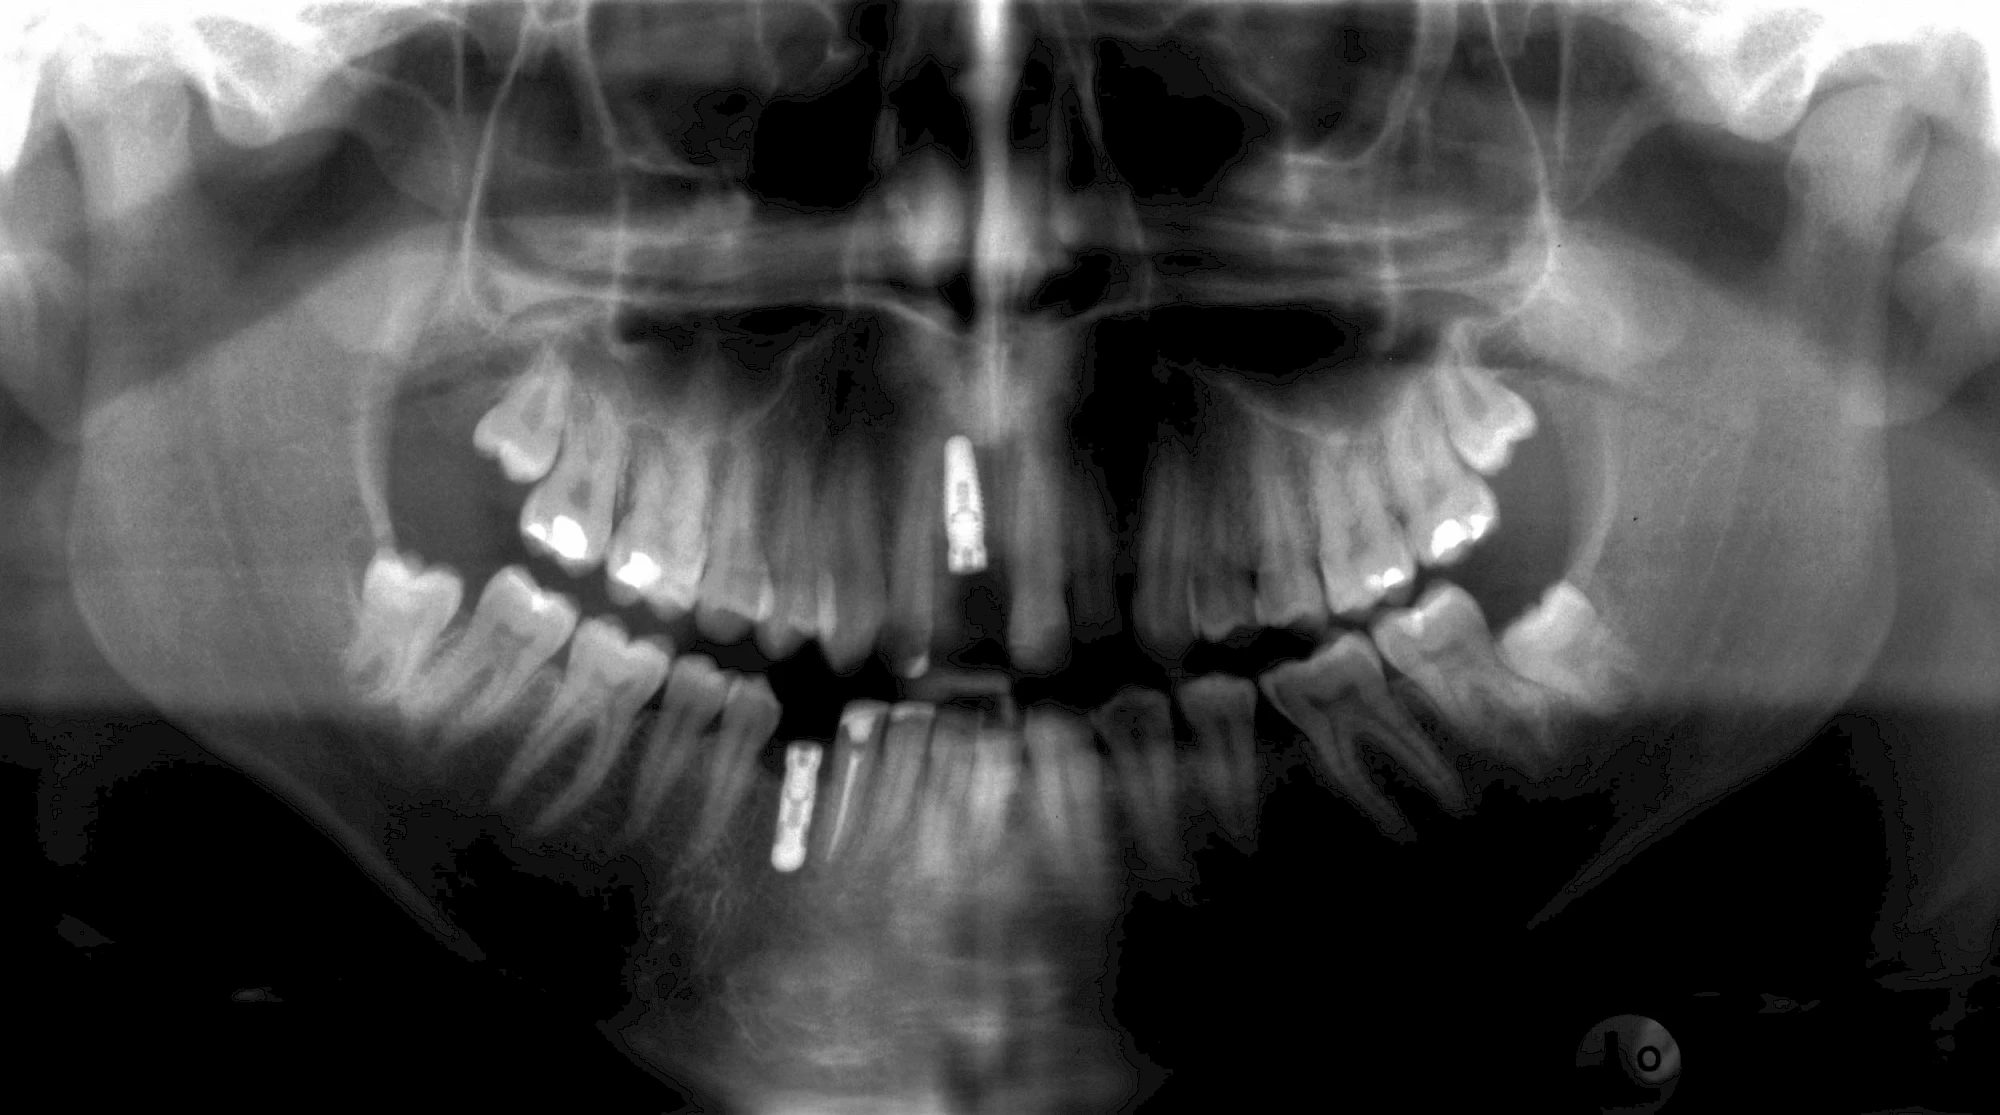

Damit Implantate an der richtigen Stelle im Kieferknochen platziert werden könen, gibt es heute vielfältige Möglichkeiten der Planung. In vielen Situationen kann die Erfahrung des Zahnarztes ausreichend sein.

Nicht selten ist jedoch auch eine technisch aufwändigere Vermessung im Vorfeld sinnvoll, z. B.:

- Wenn sich der Kieferknochen abgebaut hat

- Wenn der Nervverlauf im Unterkiefer beachtet werden muss

- Wenn die Ausdehung der Kieferhöhle im Oberkiefer beachtet werden muss

- Wenn wenige Restzähne keine gute Orientierung erlauben

In diesen Fällen kann die Planung mittels verschieden aufwendiger Röntgen-Techniken (Übersichtsaufnahme, DVT) ggf. unter Zuhilfenahme speziell angefertigter Planungsschablonen sinnvoll sein.

Knochenaufbau und Implantateinsatz

Ist nicht genügend Knochen zur Verankerung eines Implantates vorhanden, kann über einen sogenannten Knochenaufbau die Möglichkeit für das Einbringen eines Implantates geschaffen werden. Dazu kann z. B. Knochen aus der Kieferwinkelregion oder auch aus der Kinnregion entnommen und im Bereich der Fehlstellen aufgetragen werden. Auch künstliches Knochenmaterial kann dabei zum Einsatz kommen.

Im Oberkiefer wird – wenn ein Knochenaufbau notwendig ist – der Knochen in der Regel nicht außen "aufgelegt", sondern es wird der Boden der Kieferhöhle entweder über den Implantat-Bohrkanal durch Verdichtung nach oben gedrückt (interner Sinuslift) oder über eine Fensterung der vorderen knöchernen Kieferhöhlenwand kann Knochen im Bereich des Kieferhöhlenbodens eingebracht (externer Sinuslift).